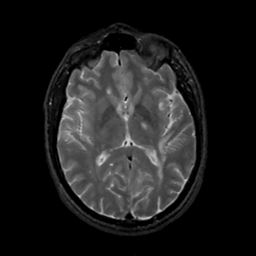

MR Study #1, February 10, 1991 -- Slice #26